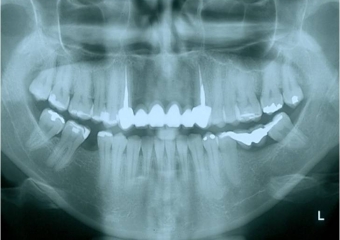

Raio x inicial